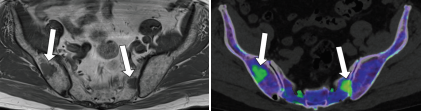

80–90keV VMI能区分正常和梗死脑实质